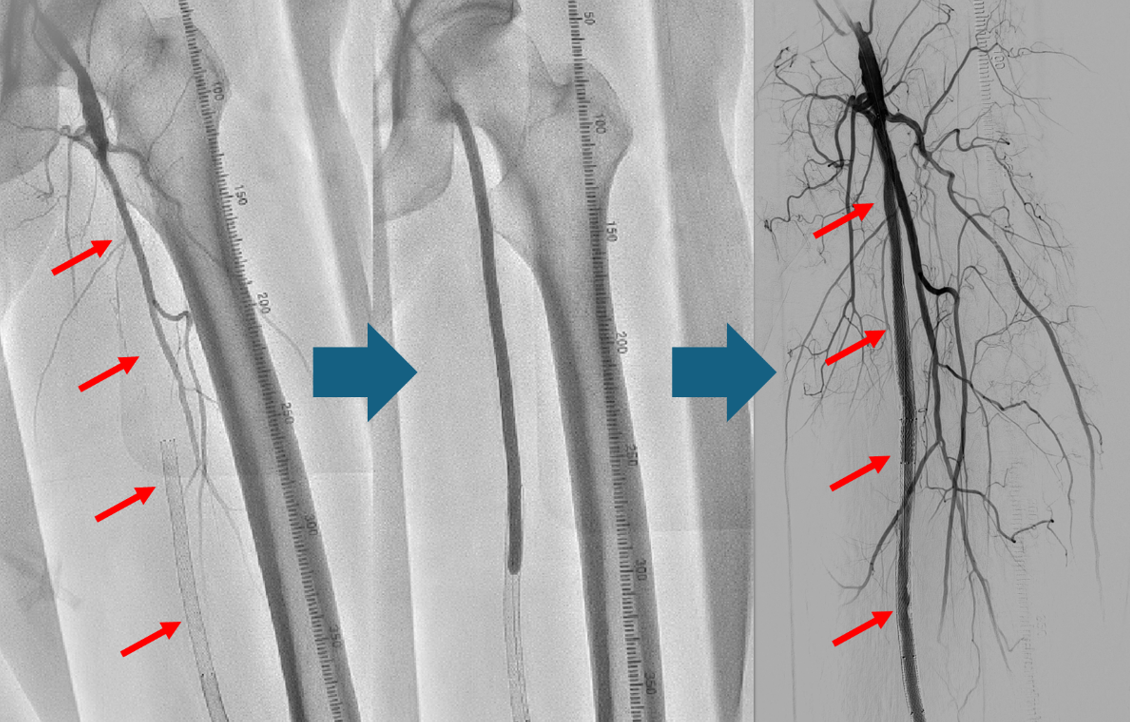

DCA(方向性冠動脈粥腫切除術)

冠動脈のプラークを切除し、体外に取り出します。プラーク量が減ることで狭窄が解除され、場合によってはステントを留置せずに治療を終えることもできます。

以下は当院で施行したDCAの症例です。赤矢印の部分に狭窄がありましたが、DCAで削り取ることで、ステントを留置することなく治療を終えました。術後数年経過しますが、再狭窄なく病状は安定しております。

症例紹介

症例患者様:60歳代 男性

症例治療内容:DCA(方向性冠動脈粥腫切除術)にてプラーク切除後に薬剤溶出性バルーンで拡張し良好に開大した。

症例治療回数:1回

(図3)浅大腿動脈閉塞に対してバルン拡張およびステント留置で治療した症例

症例患者様:70歳代 男性

症例治療内容:重症の間欠性跛行症状があり、ワイヤー通過後バルーンにて拡張。

症例入院期間・回数:3泊4日、1回